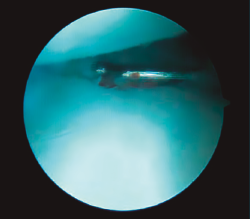

Tratamiento con control artroscópico

La asociación de osteosíntesis con tornillo de compresión por vía percutánea y la artroscopia de muñeca para el tratamiento de fracturas agudas, retardo de consolidación y pseudoartrosis de escafoides carpiano ofrece una serie ventajas con buenos resultados clínicos(37,38,39,40,41,42), como son la preservación de la vascularización del escafoides y de los ligamentos extrínsecos del carpo, permite una valoración precisa del desplazamiento, conminución e inestabilidad del foco de fractura, diagnóstico de lesiones de ligamentos asociadas y control del punto de entrada del tornillo en el polo proximal y de la introducción completa del tornillo mediante visión directa.

Se comienza la artroscopia en la articulación radiocarpiana a través del portal 3/4 con la colocación de la óptica para realizar un recorrido articular con el fin de identificar la existencia de lesiones asociadas o valorar fracturas del polo proximal del escafoides (Figura 8).

Figura 8. Visualización de la fractura de escafoides desde el portal 6R.